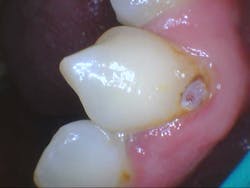

- Teeth nos. 14 and 15 both had supererupted into the 18 and 19 space (figure 2).

- Additional caries were noted on nos. 10, 11, 14, 26, 27, and 29—primarily facial/buccal caries (figures 3–8)